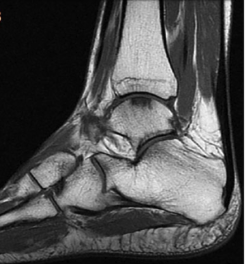

Imaging plays an important role in diagnosis. X-rays may be used to assess joint alignment and rule out associated bone injury, while MRI is often helpful for identifying cartilage defects, bone bruising, and associated soft-tissue pathology.